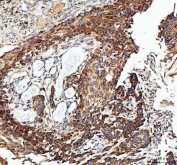

IHC staining of FFPE human esophageal squamous carcinoma tissue with IDH3G antibody. HIER: boil tissue sections in pH8 EDTA for 20 min and allow to cool before testing.

IHC staining of FFPE human rectum adenocarcinoma tissue with IDH3G antibody. HIER: boil tissue sections in pH8 EDTA for 20 min and allow to cool before testing.

IHC staining of FFPE human liver cancer tissue with IDH3G antibody. HIER: boil tissue sections in pH8 EDTA for 20 min and allow to cool before testing.

IHC staining of FFPE human placental tissue with IDH3G antibody. HIER: boil tissue sections in pH8 EDTA for 20 min and allow to cool before testing.

IHC staining of FFPE rat heart tissue with IDH3G antibody. HIER: boil tissue sections in pH8 EDTA for 20 min and allow to cool before testing.